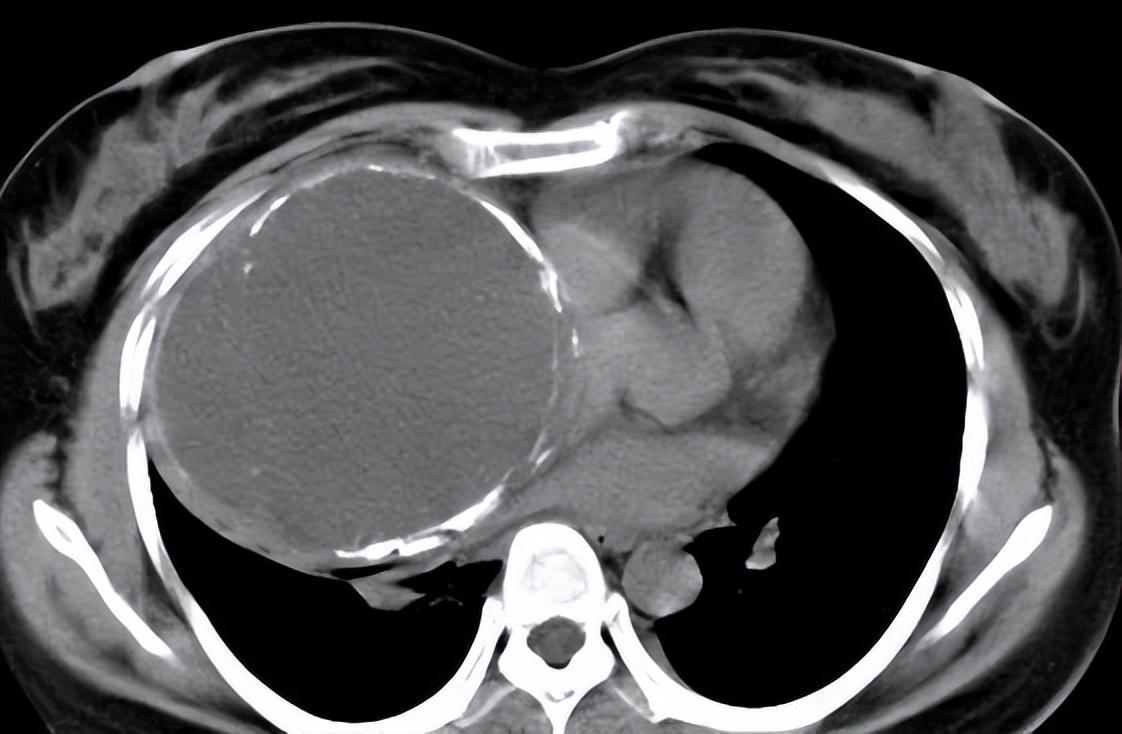

小美是一名高中女学生,当他在准备高考前进行体检时,医生检查出了他的子宫内出现了大量的黏液物质和投放,经过医生详细的询问情况,终于了解到了事情的重要起因。

如今身体当中的畸胎瘤体积变得越来越大,甚至已经对自己的子宫形成了压迫,所以需要通过手术来进行消除,可是在手术的过程当中,医生还发现他的畸胎瘤当中含有大量的头发和黏液物质,而这即便是完成了手术也不能完全去掉。